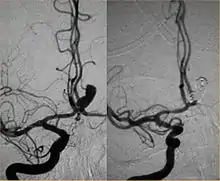

Parallel to the development of catheters, in the radiology and neuroradiology units, image technology dramatically improved: Charles Mistretta in 1979 invented digital subtraction angiography (DSA), the technique currently in use. It consists of performing skull radiography under basic conditions which are then "subtracted" to the image after contrast media injection, to provide an image where only brain vessels are displayed, with great improvement in the diagnostic potential.